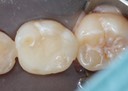

Alan Chinn #20 finish